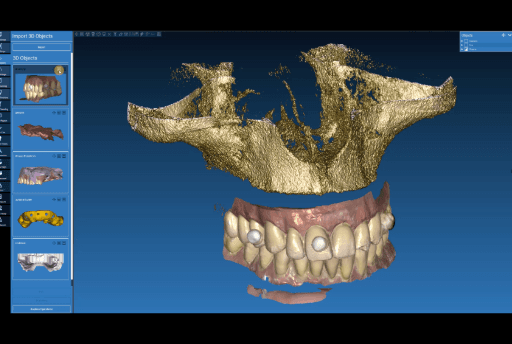

The digital wax-up was done by the dental lab based on the digital patient data provided. This wax-up will be adapted by the lab with the final implant positions on the day of the surgery.

Temporary full-arch implant-supported appliances for the upper and lower arch designed in exocad

Wax-up done in exocad upon the digital patient.

Temporary full-arch implant-supported appliances for the upper and lower arch designed in exocad upon the digital patient.

3.4 Adaptation of the wax-up by the dental lab and receiving STLs for in-house production

While the patient is in the dental chair, the dental lab adjusts the wax-up considering the intraoral data with the final implant positions in exocad. The temporary full-arch implant-supported prosthesis are then exported as STL files and sent via email to the clinic for in-house manufacturing.